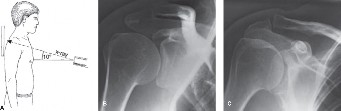

Physicians should obtain a complete set of x-rays. Special views include the modified Westpoint axillary (Fig. 2–43B) to evaluate for glenoid loss and the stryker notch view (Fig. 2–43A) to evaluate the Hill–Sachs lesion. This view brings the posterolateral defect into direct visualization. 3D CT imaging is also very useful for evaluating glenoid bone loss and estimating the size of the Hill–Sachs lesion.

--- _Figure 2–43_A: Stryker notch view. B: West point axillary view. (From Bucholz RW and Heckman JD. Rockwood and Green’s Fractures in Adults 7e. Philadelphia: Wolters Kluwer, 2009.)

The best view to visualize a Hill–Sachs lesion on radiographs is?

- With the patients hand above his head and the x-ray beam directed 10 degrees cephalad

Discussion

The correct answer is (A). This describes the stryker notch view, which is the best way to visualize the posterolateral humeral head where a Hill–Sachs lesion is most commonly located. Answer B describes a Zanca view, which is used to visualize the AC joint. Answer C does not have a common eponym, although this view can be helpful when evaluating proximal humerus fractures, glenohumeral arthritis, or glenoid fractures. An axillary view (Answer D) is useful when evaluating anterior or posterior dislocation. A serendipity view (Answer E) is taken with the beam directed 40 degrees cephalad aiming at the clavicle; it is used to visualize the SC joint and the clavicle. CASE 16 A 56-year-old male presents to your clinic 2 months after a polytrauma MVA. He was in the ICU, intubated for a week after his initial injury, and has trouble recounting the details of his hospitalization. He does recall being diagnosed with a frozen shoulder. He is currently at a rehabilitation facility and has noticed